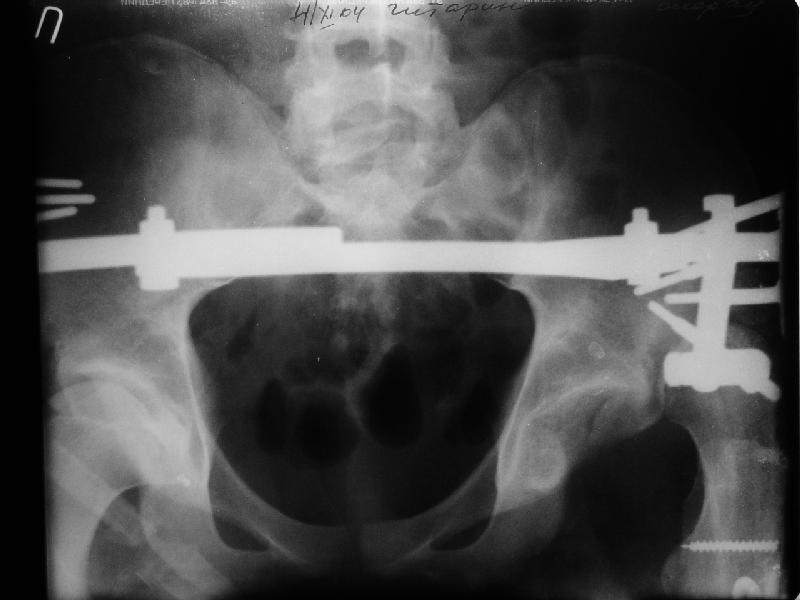

Уважаемые коллеги,пожалуйста, подумайте над следующим ребусом. В нашу клинику поступилпациент из области, 17лет, получивший травму в ДТП 25.08.04, открытый перелом бедра, при поступлении наложено скелетное вытяжение.

30.09.04 на операции выявлен вывих бедра и перелом голени на этой же стороне. Остесинтез бедра все же выполнен, и по заживлении раны пациент переведен к нам. Кроме того у пациента нейропатия седалищного нерва на этой же стороне. В нашей клинике планируется наложение аппарата таз-бедро, для постепенного низведения бедра с последующим открытым вправлением, замена фиксатора на запираемый гвоздь и блокируемый остесинтез голени. Вариант с первичным эндопротезированием мы не рассматривали из-за юного возраста пациента. Вопрос с чего начать? Кроме того, сгибание в коленном суставе в настоящее время (95 градусов) затрудняет остеосинтез голени.Стоит-ли менять гвоздь? Или же спилить торчащий конец во время открытого вправления? Может, попробовать все сделать одномоментно? Заранее спасибо.

Просьба простить за длительное молчание, не было фотоаппарата, чтобы перенести рентгенограммы. Больного прооперировали в прошлый четверг, как и предполагали, голень проблем не доставила(настолько, что даже не ввели дистальные винты по ряду причин: срок после травмы, целая малоберцовая, последующая длительная ходьба без нагрузки, да и гвоздь сел плотно). Изначально планировали после удаления фиксатора антеградно завести стержень и утопить конец, но вопрос был исчерпан, когда выяснилось, что все имеющиеся стержни слишком длинные, пришлось ретроградно забить большеберцовый гвоздь, после рассверливания; серьезные проблемы возникли с устранением ротации. В вертельной области сломали стержень-джойстик(привет установщику эндопротеза), дальнейшие манипуляции проводили пучком спиц и стержнем с кондуктором. Закончили все аппаратом таз-бедро. Решили что возможные огрехи с ротацией устраним после открытого вправления. Снимки прилагаю. Спасибо за участие в обсуждении. Обязуюсь информировать о дальнейших этапах лечения.